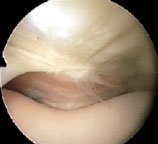

A plica may also be like a band of tissue. This image is of a suprapatellar plica viewed from the lateral suprapatellar portal, bowstringing and snapping across the supra patellar pouch over the medial femoral condyle. In this image, the red arrow is pointing to the plica. The little black arrows show the joint surface of the patella and femur.

The blue arrow shows the inflamed area of the femur where the plica has been snapping. This would be completely invisible from the lower portals.